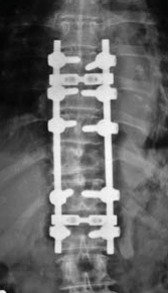

Madam B, a 72-year-old female, presented to my clinic recently with 3 months history of low back pain radiating to her left supra-iliac region. Her symptoms had worsened progressively. She had tenderness elicited by lumbar spine flexion. Neurological examination of her lower limbs was normal. X-ray and MRI of her spine revealed an extensive infiltrative lesion of T11 vertebral body, and its left pedicle. The posterior wall of the vertebra was eroded, and the lesion was encroaching onto the spinal cord and compressing it. The assessment was an extensive T11 spinal metastasis with cord compression and high risk of pathological fracture that could result in paralysis. Madam B underwent T11 decompression laminectomy with clearance of tumor tissue immediately surrounding the cord. The spine was instrumented from T8 to L1 segments to provide stability and to pre-empt pathological fracture. Frozen section of the specimen taken during surgery indicated the lesion to be lymphoma. This was later sub-typed as diffuse large B-cell lymphoma. Her back pain resolved completely following the surgery and she was ambulating well. She was referred to hematologist for outpatient chemotherapy treatment which started one week following the surgery.

Surgical approaches may be anterior or posterior. Sometimes a combination of both approaches is necessary. Surgery is needed if patient presents with deteriorating neurological deficit due to spinal cord compression, or when there is imminent risk of pathological vertebral fracture. Radiotherapy or chemotherapy may not be able to remove the tumour compressing the cord fast enough. They also can not address the pain arising from spinal instability due to pathological fracture. Speedy surgical decompression is needed in such circumstance to preserve the spinal cord function. Following surgery, patient will have good pain relief and can be treated with chemotherapy or radiotherapy without fear of losing the neurological function.